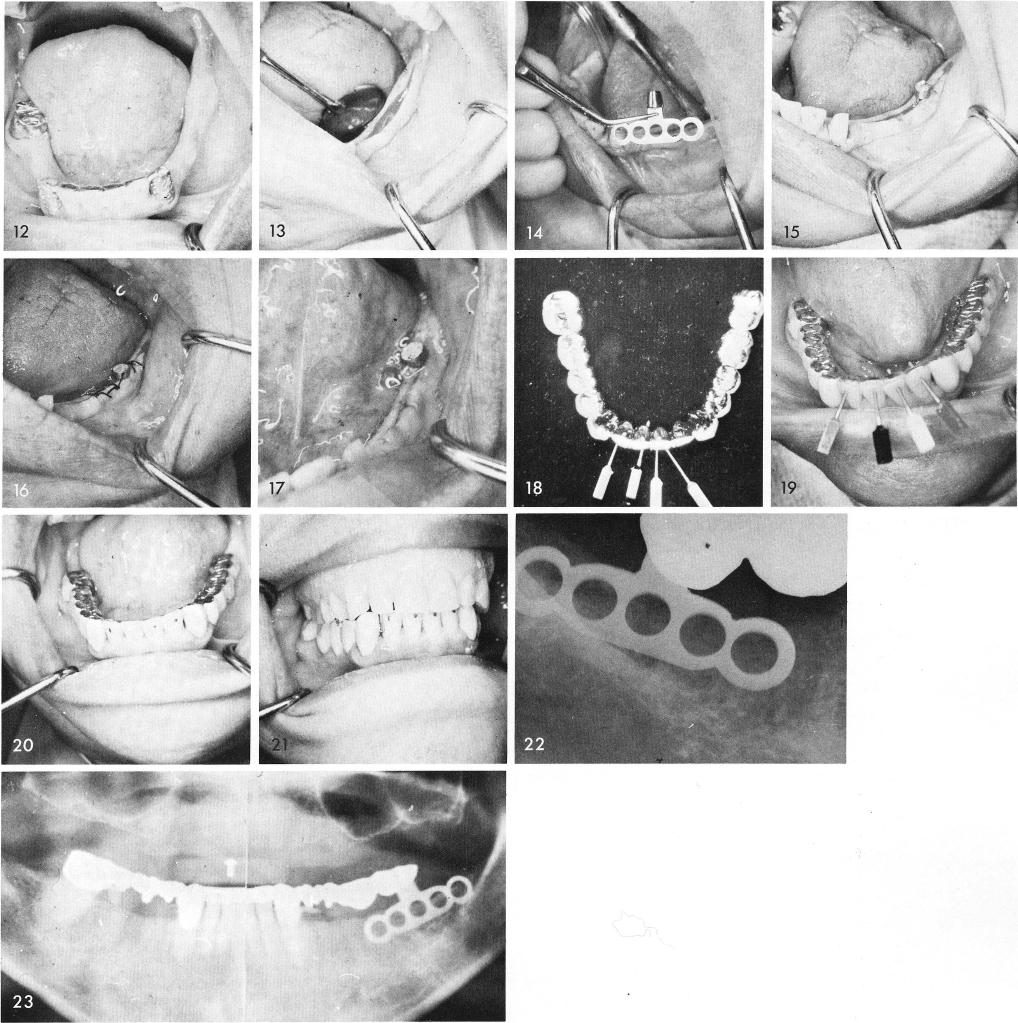

The tissues were then incised and reflected, fig. 13, exposing the knife-edge ridge and the earlier designed bladevent was inserted, figs. 14, 15, and sutured, fig. 16. After the sutures were removed, fig. 17, the acrylic veneer bridge was completed, fig. 18, and cemented into place with the non parallel pins cemented and "screwed" into position, figs. 19, 20, 21. Fig. 22 was the post-operative periapical film revealing the bladevent and fig. 23 shows a panoramic x-ray.

1 Acrylic veneer bridge cementation over mandibular implants using pins